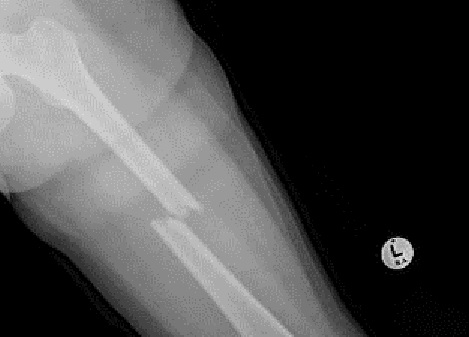

Fig6. - Midshaft tibia fracture.

Fig6. - Treated with an intramedullary nail